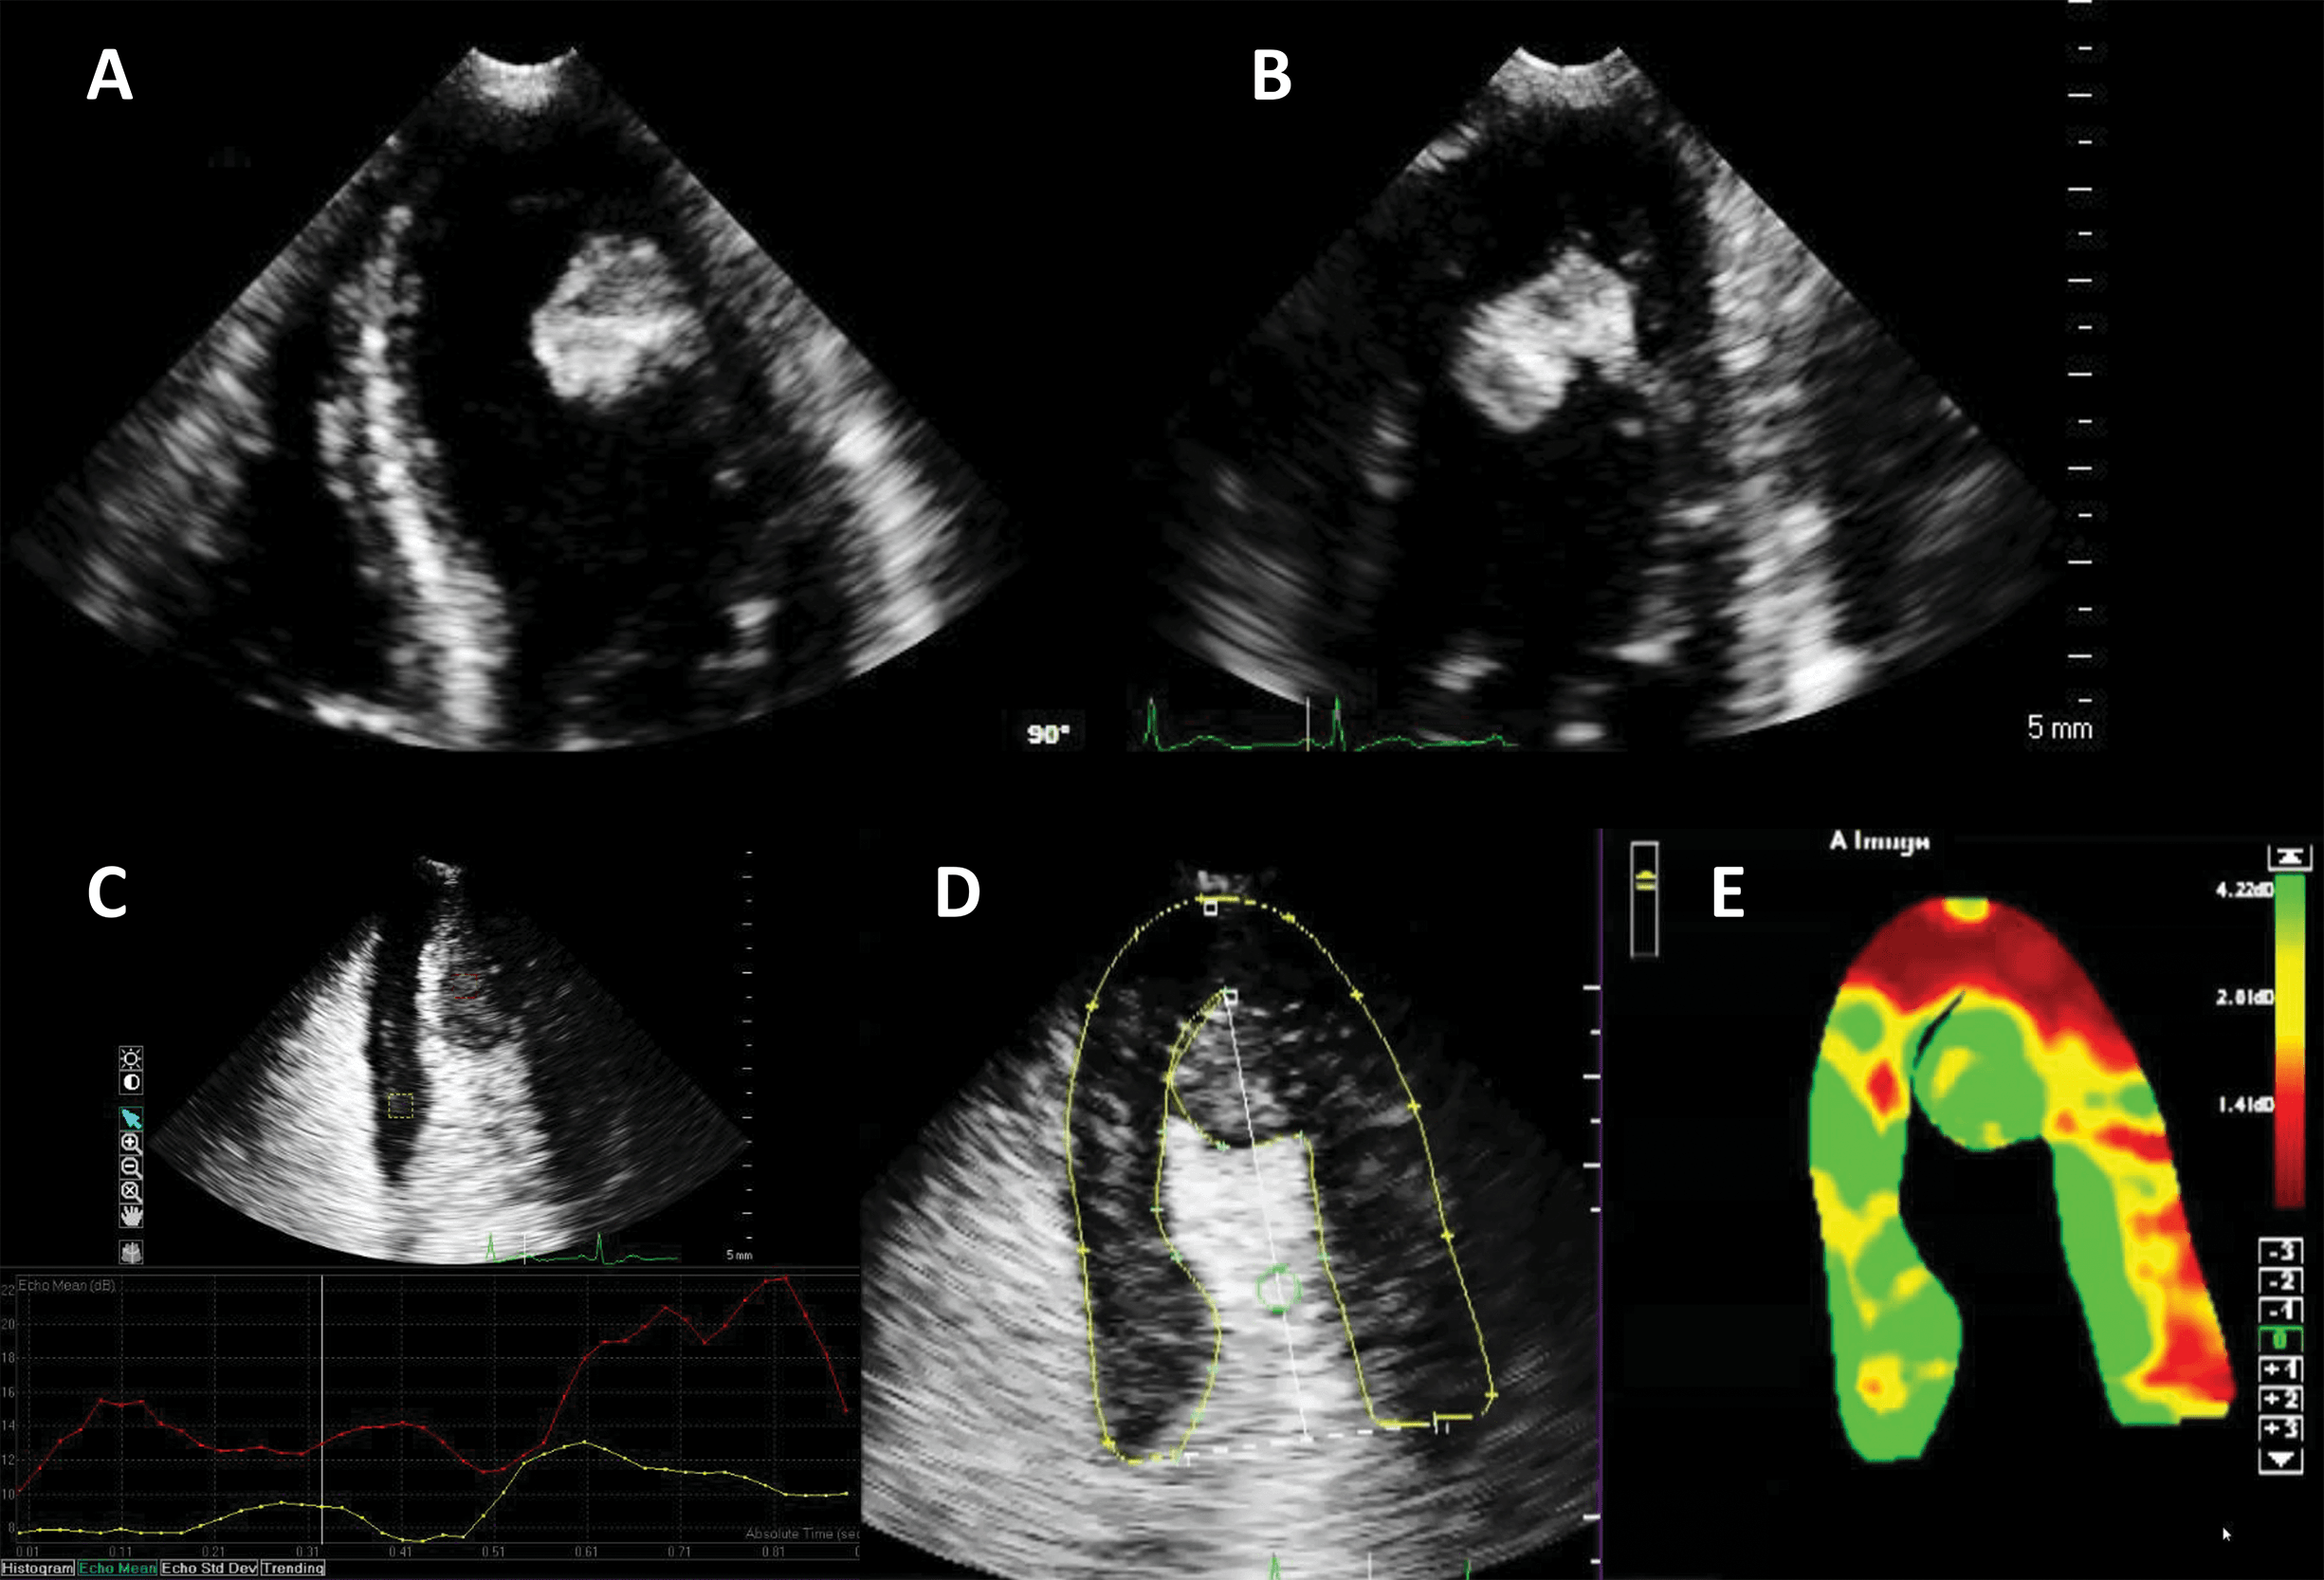

Another application of LVO is morphological diagnosis, particularly in disease states which manifest in the artefact-prone LV apex. Beside possible foreshortening, the LV apex is prone to clutter and reverberation artefacts, while also having a weaker potential to generate harmonics because of its position in the near-field in apical views [28]. As such, apical forms of hypertrophic cardiomyopathy [29, 30], eosinophilic cardiomyopathy [31] and non-compaction cardiomyopathy [32] may escape detection with unenhanced ultrasound.

Numerous case reports and case series document the use of UEA in these instances [29, 30, 31, 32, 33]. Studies have also been performed demonstrating the added value of contrast-enhanced ultrasound in hypertrophic cardiomyopathy [34] (Fig. 4, Video 4).

Fig. 4.Hypertrophic cardiomyopathy patient with very poor image in apical 4-chambers view. (A,B) Native images, end-diastole (A) and end-systole (B). The endocardium of the lateral wall is not visible, and the apex cannot be seen. (C,D) Contrast-enhanced images, in the same moments in the cardiac cycle. The LV contour is clearly delineated, during systole there is complete cavity obliteration, with an apical aneurysm (arrow). Source: personal collection.